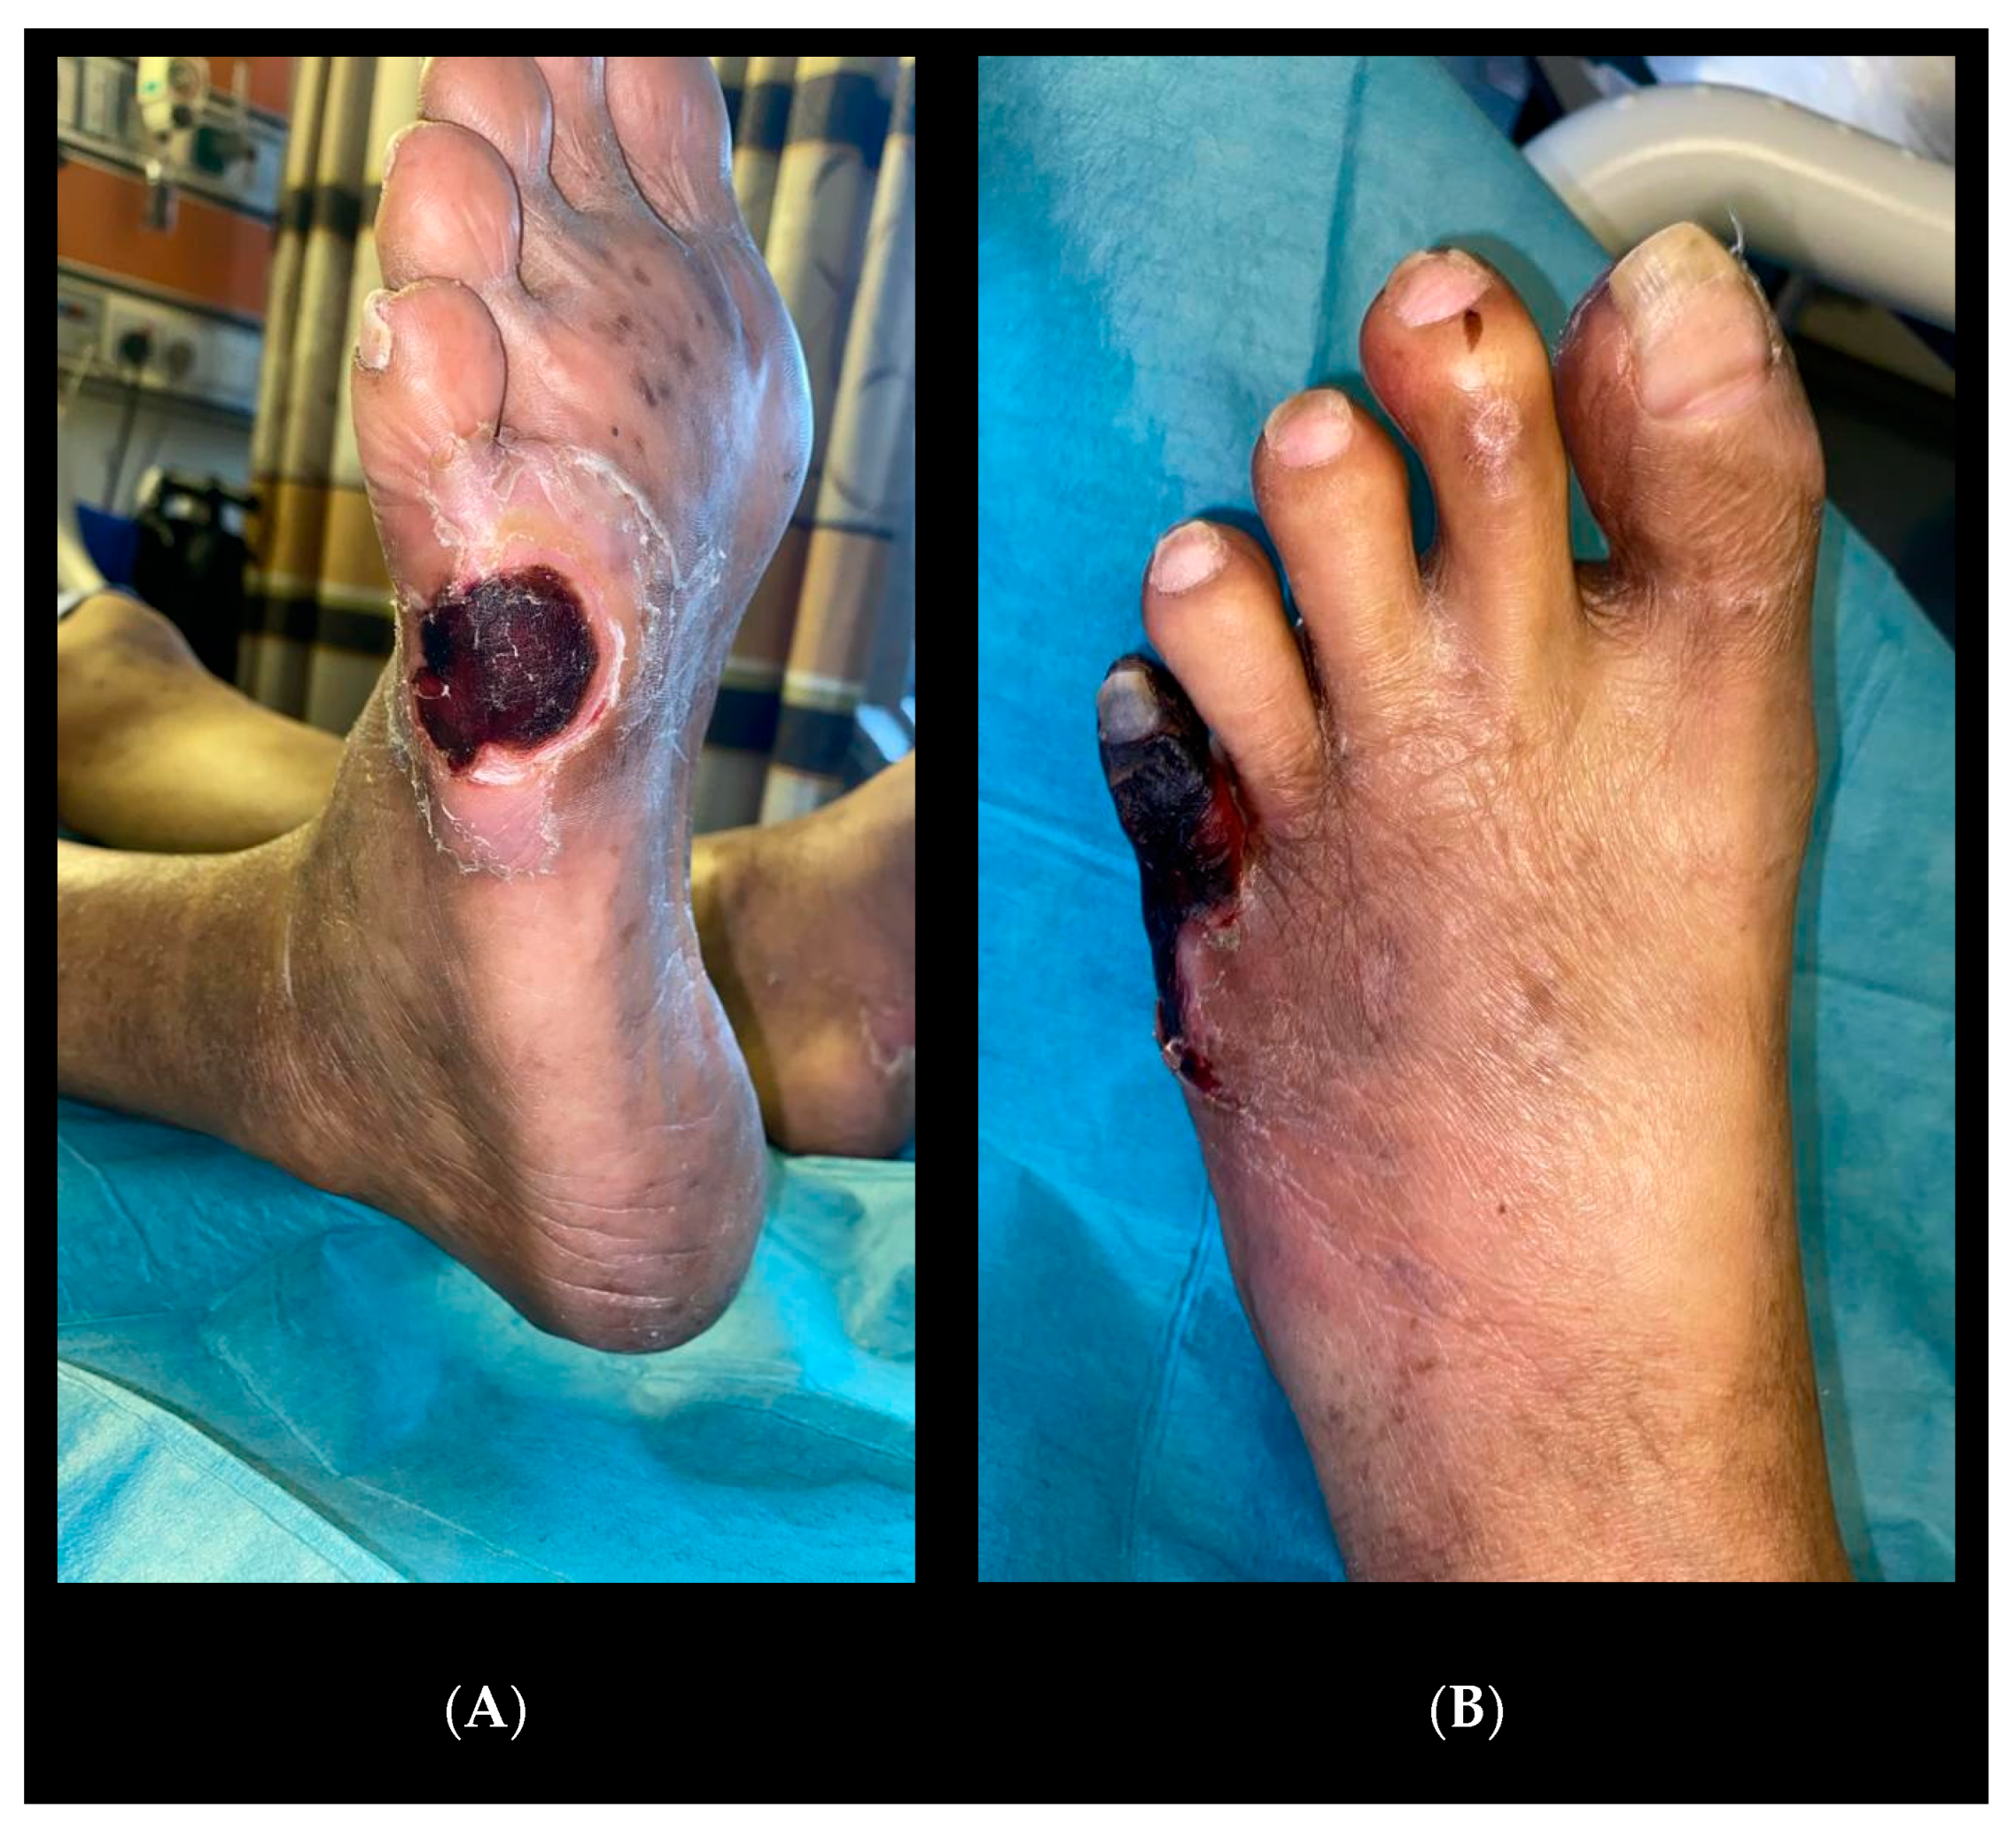

He was started on neoadjuvant chemotherapy with a view for the definitive Whipple procedure. He was subsequently referred to the vascular unit for bilateral fifth toe gangrene (Figure 2) that had begun as ulcers from poorly fitted shoes. He complained of increasing rest pain in the leg with purulent discharge from the left side, as well as fever, chills, and rigors.

The patient’s wound (Figure 5) recovered with a combination of culture-directed antibiotics, vacuum dressing, and motivation from a supportive family.

Figure 5. (A) Right foot wound. (B) Left foot wound.